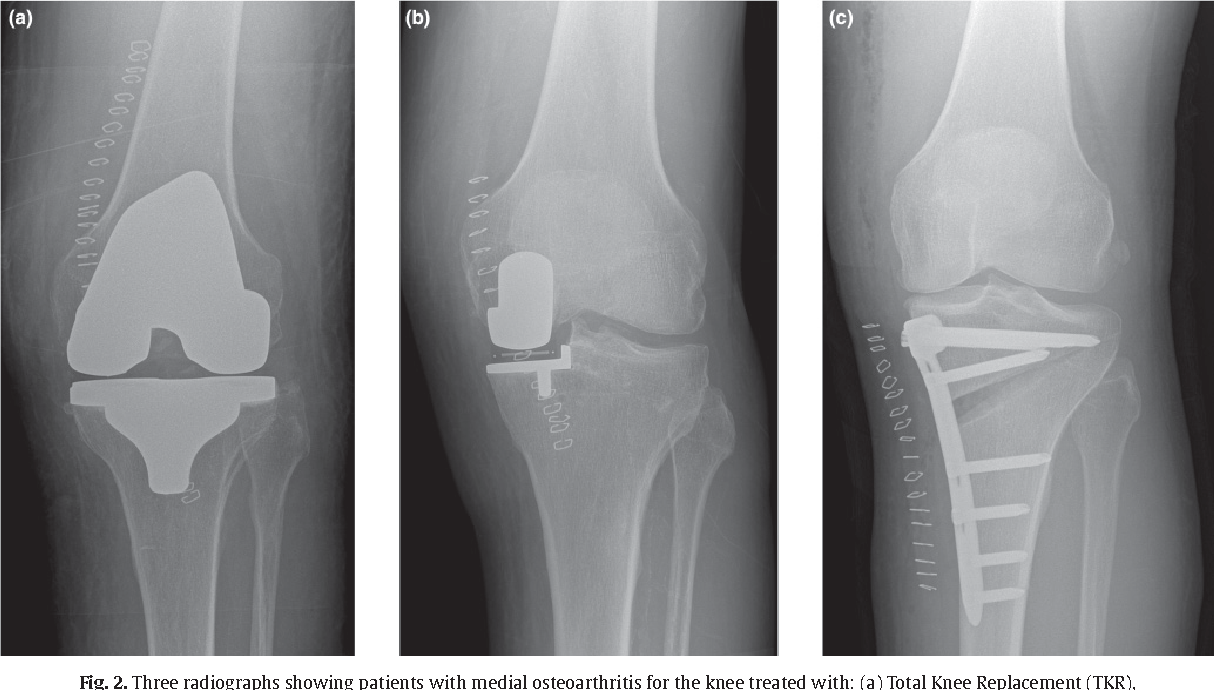

• Osteotomy (usually a high tibial osteotomy, HTO): realigns the leg to shift load off the worn compartment, preserving your native joint.

• Unicompartmental knee replacement (UKR): resurfaces only the damaged side with metal and plastic.

Conversion to Total Knee Replacement after undergoing Osteotomy or UKR results in similar outcomes, although there may be slightly better early return to function and less need for augments in the osteotomy to TKR group of patient